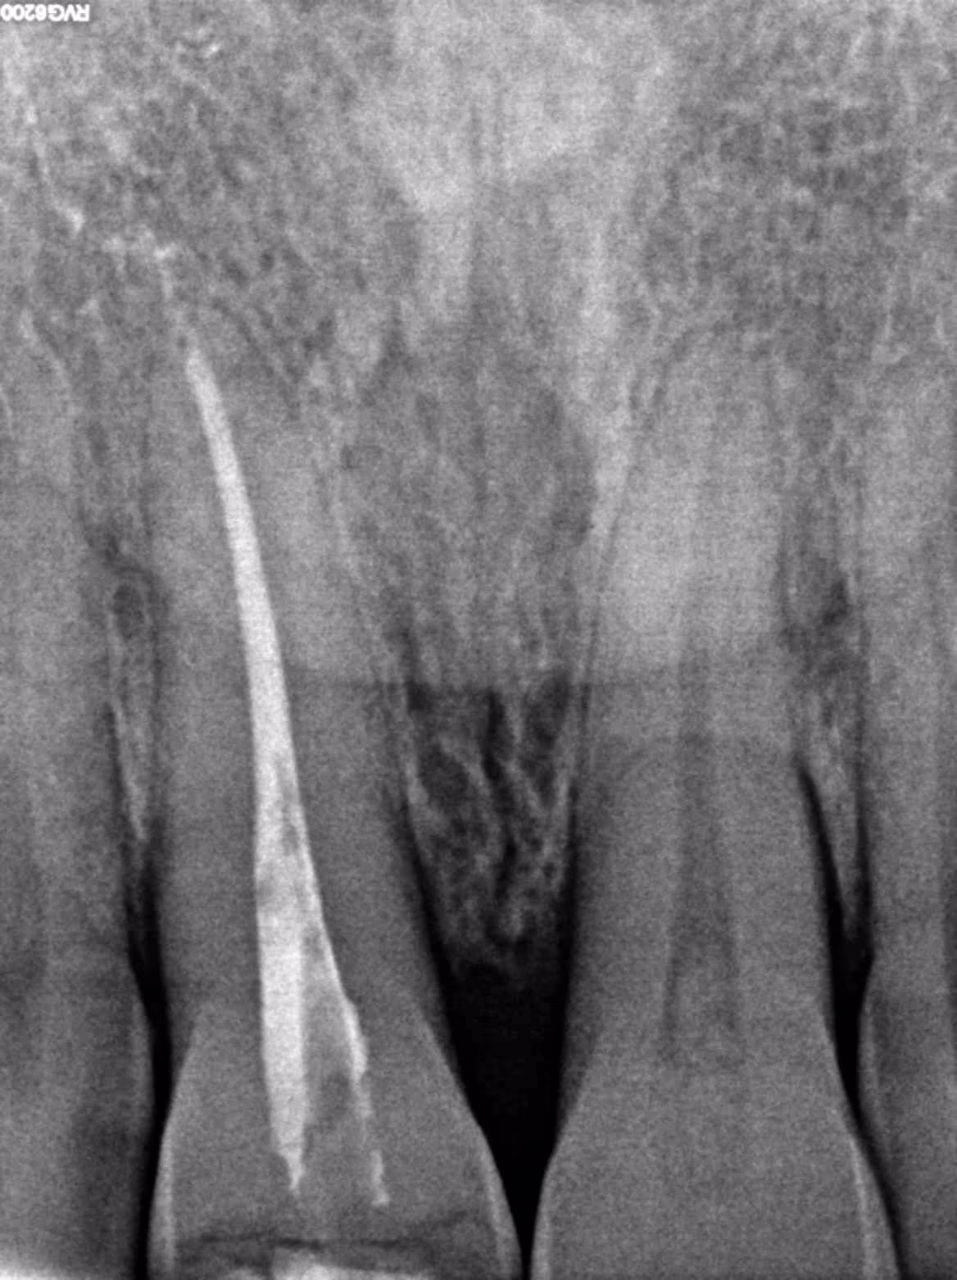

Зуб 11 із раніше виконаною композитною реставрацією. В анамнезі – ендодонтичне лікування понад 5 років тому. Зуб відновлений із застосуванням скловолоконної штифто вої конструкції та композиту.

За даними КТ: кореневий канал обтурований гомогенно до апекса, ознак апікальних змін немає. Одиничну кишеню не виявлено. Стан тканин пародонта – у межах норми.